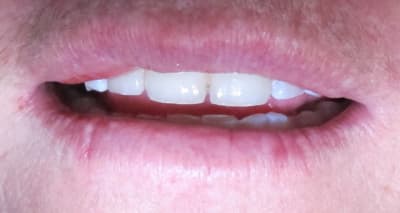

1er bridge full Zircone

Je suis prêt pour les critiques n'hésitez pas.

Oui les photos sont mauvaises.

J'aurai bien aimé une photo sans l'amovible, mais à mon avis il était possible de faire autre chose qu'une fausse gencive céramique moche.

Si le patient est démuni, joli boulot.